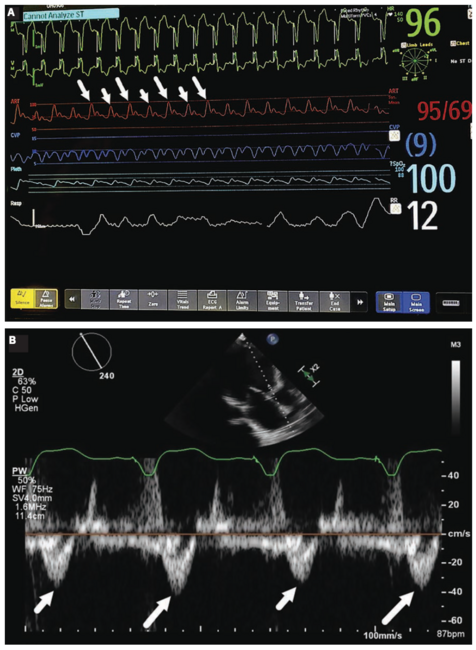

A 61-year-old man with inotrope dependent systolic heart failure secondary to nonischemic cardiomyopathy presented to the emergency department with worsening dyspnea and weight gain. On exam, his blood pressure was 85/66 mmHg, heart rate of 95 beats per minute with a regular rhythm, with jugular venous distension, a third heart sound, and 3+ pitting edema. The radial artery pulse was weak with variable intensity. An echocardiogram showed an ejection fraction of 10% and a trivial pericardial effusion without tamponade. Invasive monitoring in the intensive care unit revealed a regular alternating arterial pulse amplitude, independent of the rhythm or the respiratory phase (Figure 1A). A similar pattern was observed on pulse wave Doppler of the left ventricular outflow tract by echocardiography (Figure 1B). The patient was treated with intravenous diuretics and an intra-aortic balloon pump. He ultimately underwent cardiac transplantation.

The term pulsus alternans has been used inaccurately to describe any pulse of variable amplitude, referred to as “false alternans”.3 Pulsus alternans is a physical exam phenomenon identified by arterial palpation, observation of the arterial pressure waveform, or plethysmography (Oximetry Alternans). It is important to distinguish true pulsus alternans from other causes of variable arterial pulse since the clinical implications vary. There are two proposed mechanisms explaining pulsus alternans. The first involves the Frank-Starling relationship whereby beat-to-beat proportional variations in end-systolic and end-diastolic volume result in variation of the contractile force generated. The second mechanism relates to abnormal intracellular calcium handling, resulting in fluctuations in myocardial contractile force, and therefore, forward stroke volume.2 In addition to pulsus alternans, the differential diagnosis of a variable pulse includes pulsus paradoxus, normal respiratory variation, and arrhythmias (Figure 2). Pulsus paradoxus is a pathologic decrease in systolic blood pressure during inspiration of greater than 10 mmHg. The arterial pressure reduction is sustained during the inspiratory portion of respiration and does not vary from one beat to the next (Figure 2B). Pulsus paradoxus is classically associated with cardiac tamponade, acute asthma, and chronic obstructive pulmonary disease exacerbations.4 Variations in respiration or cardiac cycle length can respectively affect venous return and diastolic filling time with subsequent effects on the arterial pulse, which may be confused with pulsus alternans.5 A physiological decrease in arterial pressure during normal inspiration can occur (Figure 2C). Furthermore, arrythmias such as bigeminy can produce alternating strong and weak beats, however the rhythm would be irregular and weak beats would occur prematurely.5 Finally, electrical alternans, which bears a similarity in name and is typically seen in the presence of a swinging heart within a large pericardial effusion, refers to beat-to-beat alternation of the axis or amplitude of any electrocardiographic component (QRS complex, P wave, ST segment, T wave), and not the arterial pulse.